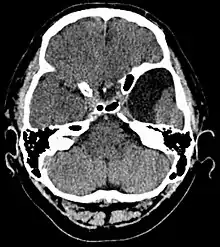

| Arachnoid cyst | |

| An MRI of a 25-year-old woman with left frontotemporal arachnoid cyst. | |